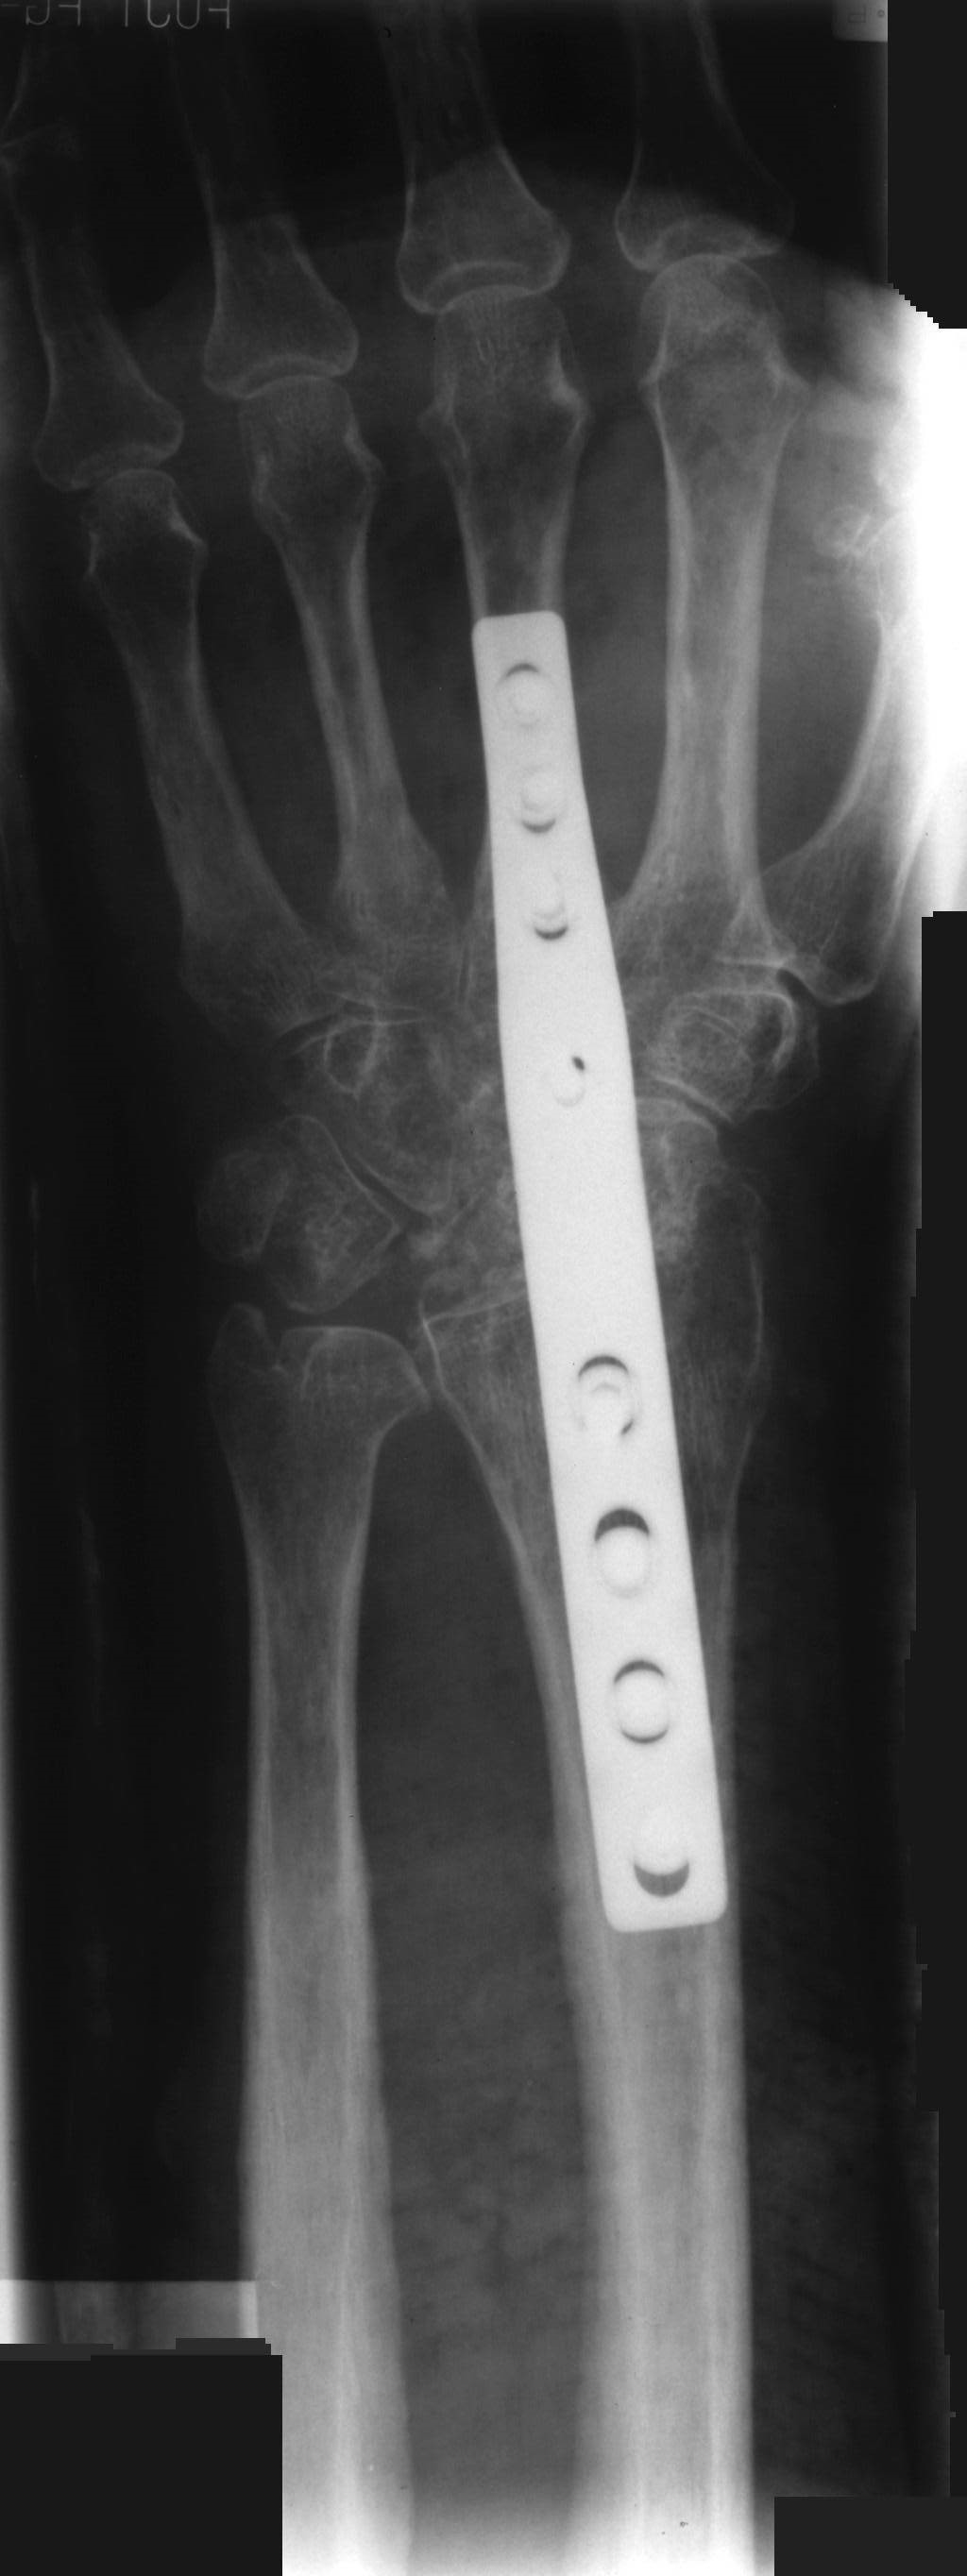

Om operationen